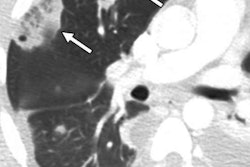

37-year-old man with history of broken needle proximal to the right elbow while injecting heroin. Anterior-posterior x-ray view of right humerus shows three linear hyperdensities in the soft tissues of the arm (arrows). Image courtesy of RSNA."In some cases, we found septic emboli in the lung or brain," Flores said in a statement released by the RSNA. "As these patients start having to access larger veins, they become more prone to these types of infections."